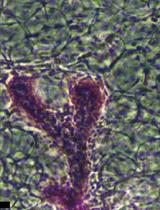

The mammary gland undergoes extensive remodeling during pregnancy and is also subject to neoplastic processes both of which result in histological changes of the gland epithelial structure. Since the mammary tree is a complex three-dimensional structure a method is needed that provides an overview of the entire gland. Whole mounts provide this information, are inexpensive and do not require specialized equipment. This protocol describes mammary gland isolation, whole mount preparation and analysis. Mammary gland tissue, which is removed postmortem, is stained with Carmine Alum, a nuclear stain, allowing detection of epithelial structures embedded in the adipose tissue of the mammary fat pad. Stained mammary glands are imaged by light microscopy or embedded and sectioned for histological examination. Image analysis software such as Image J can be used to quantify extensity of branching complexity, epithelial structure remodeling or hyperplastic changes.

Although development of the mammary gland begins during embryonic development and a rudimentary epithelial structure is present at birth, the epithelial mammary tree undergoes extensive expansion postnatally. In response to hormonal changes, mammary epithelial cells proliferate and invade the mammary fat pad. During pregnancy, the mammary gland epithelium undergoes further differentiation and remodeling to prepare for milk production. Subsequently, these epithelial structures involute in response to weaning. These remodeling processes are driven by hormones, growth factors, cytokines and the extracellular matrix. In addition to remodeling in response to physiological processes, the mammary gland is subject to pathological processes such as neoplastic transformation. This complex biology together with the relatively ease of isolation make the mammary gland a useful experimental model. Experimental studies analyzing mammary gland biology or neoplastic transformation often employ mouse models to quantify the effect of gene deletion or overexpression on mammary gland development, remodeling and neoplastic transformation. Mammary gland whole mounts allow routine examination of these normal and disease processes on the entire 3D epithelial structure of the mammary gland (Plante et al., 2011; Inman et al., 2015; Tucker et al., 2016 and 2017; Kolla et al., 2017; Tolg et al., 2017). Furthermore, injection of mice with potential therapeutic compounds combined with whole mount analysis allows in vivo testing of future cancer treatment strategies. This protocol provides details of the procedure starting with removal of the mammary gland and ending with image analysis. A video of mammary gland isolation, photos, figures and referenced literature make it more complete compared to existing whole mount protocol.